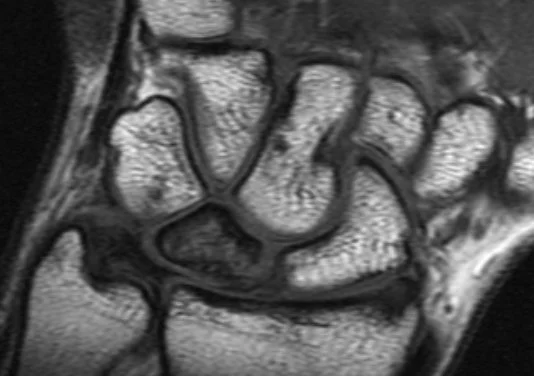

• Avascular necrosis of the lunate

• XR = sclerosis and flattening of lunate

• MRI = best test

• Sclerosis centrally (low T1 & T2)

• May see edema in acute phase